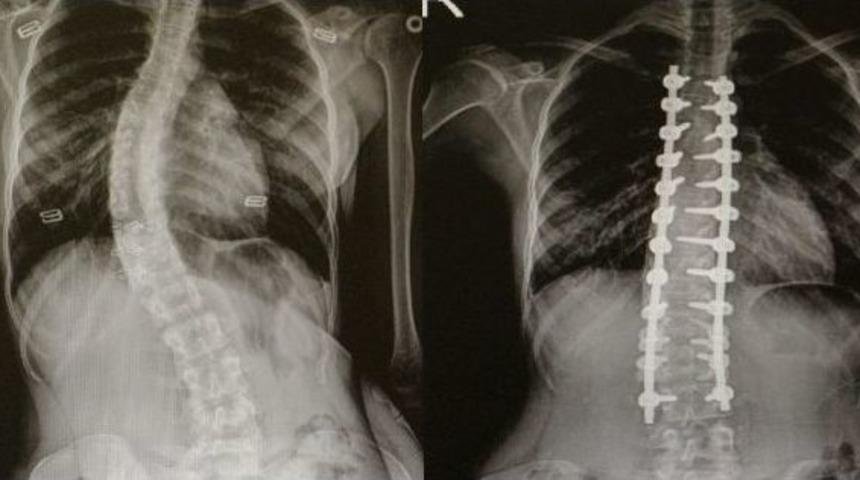

Skolyoz(omurga eğriliği) olan hastalar Ondokuz Mayıs Üniversitesi(OMÜ) Tıp Fakültesi’nde şifa buluyor.Skolyozun genellikle çocuklarda görülen bir hastalık olduğunu ifade eden OMÜ Tıp Fakültesi Ortopedi ve Travmatoloji Anabilim Dalı Öğretim Üyesi Yrd. Doç. Dr. Mesut Kılıç, omurga eğriliği olan hastaların OMÜ Tıp Fakültesi’nde rahatlıkla tedavi edildiğini söyledi. Skolyoz cerrahisinde modern tekniklerin kullanıldığını belirten Kılıç, nöromonitörizasyon uygulamasıyla felç riskini yüzde sıfıra kadar indirdiklerini söyledi.Kılıç: "Bazı hastalarda cerrahi tedavi gerektirmektedir"Skolyozun özellikle kız çocuklarda daha sık görülen bir durum olduğunu söyleyen Yrd. Doç. Dr. Mesut Kılıç, "Skolyoz hastalığı özellikle çocuklarda ve gençlerde gerek kozmetik gerekse fonksiyonel açıdan şikayetlere sebep oluyor. Tedavide çoğunlukla cerrahi dışı yöntemler uygulanır. Korse, egzersiz gibi. Fakat bazı hastalarda cerrahi tedavi gerektirmektedir. Cerrahide günümüzde modern teknikler kullanılmaktadır. Halk arasında platin diye bilinen uygulamalarla düzeltme sağlanmaktadır. Ayrıca son dönemlerde teknolojik gelişmelerle ortaya çıkan nöromonitörizasyon dediğimiz bir sistem uygulanıyor. Hasta uyutularak bilgisayara bağlanıyor. Ameliyat sırasında bir felç durumu var mı yok mu? Sinir yapılarında bir zedelenme var mı yok mu bunu bize bildiriyor. Halk arasında bu tür ameliyatlarda ’felç olursunuz’ korkusunu biz çok duyuyoruz. Fakat bu uygulama ile felç riskini yüzde sıfıra yakın indiriyoruz" dedi.Yavuz: "Artık dayanamıyordum"Skolyoz ameliyatı olan Sedef Yavuz(17), "Omurgam yavaş yavaş sağ tarafa doğru dönmeye başlamıştı. Ağrılarım oluyordu. Artık dayanamıyordum. Oturduğumda ve yürüdüğümde bunalmaya başlamıştım. Tedavimin nerede yapılabileceğini araştırdım ve OMÜ’de bu tedavinin yapıldığını öğrendim. Doktorumla konuştuk ve ameliyat olmaya karar verdim. Ameliyata gülerek girdim. Ameliyattan sonra biraz ağrılarım oldu ama şimdi çok iyiyim" diye konuştu.